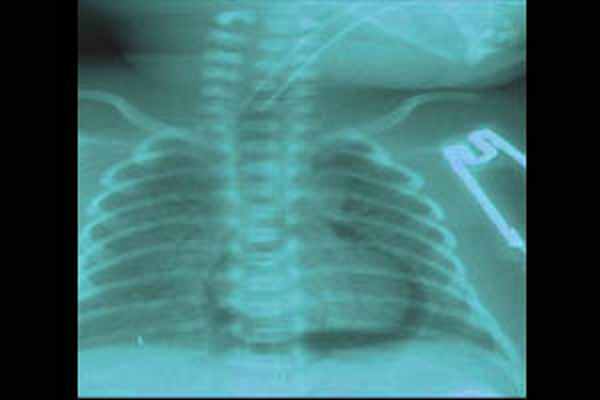

- Рентгенография ОГК. На рентгенограмме неонатолог обнаруживает просветление по периферическим отделам грудной клетки и спадение (коллапс) легкого. При этом средостение, как правило, смещено в здоровую сторону. Рентгенологическое исследование также применяется для диагностики пневмоперикарда.

Диагноз ИЛЭ ставится на основании клинических, рентгенологических и лабораторных данных. Иногда ИЛЭ диагностируется после дренирования пневмоторакса и расправления пострадавшего легкого. В большинстве случаев, выявлению ИЛЭ предшествует ухудшение состояния ребенка, снижение оксигенации, необходимость увеличения параметров ИВЛ, десинхронизация с аппаратной вентиляцией, тенденция к артериальной гипотензии. При объективном осмотре у ребенка могут наблюдаться вздутие грудной клетки, крепитирующие хрипы на стороне поражения. Лабораторно выявляются гиперкапния, гипоксемия и ацидоз. Классическая рентгенография грудной клетки в прямой проекции лежа позволяет четко диагностировать ИЛЭ, которая проявляется в двух основных формах: линейной и кистозноподобной. Часто эти две формы выявляются вместе. Линейная ИЛЭ визуализируется как неразветвленные тени длиной от 3 до 8 мм, ширина их редко превышает 2мм. Кистозноподобная форма представляет собой округлые, иногда овальные, тени от 1 до 4 мм в диаметре. Иногда данная рентгенологическая картина ошибочно интерпретируется как нормально аэрированное легкое, окруженное экссудатом, как при аспирационном синдроме или отеке легких. Линейную форму необходимо дифференцировать от «воздушных бронхограмм» при РДС. «Воздушные бронхограммы» представляют собой протяжённые разветвлённые тени, напоминающие трахеобронхиальное дерево, постепенно уменьшающиеся и исчезающие к периферии. Линейная форма ИЛЭ видна в дистальных отделах лёгких, в стороне от бронхов и не имеет ответвлений.

Пневмоперикард